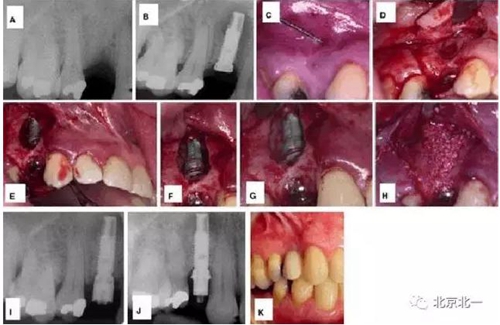

对于种植体周围炎引起的骨缺损,有学者应用骨替代材料取得了很好的治疗效果。Quirynen 等应用去蛋白的牛骨粉成功的治愈了种植体周围炎引起的骨缺损,治疗方法如图 1。

图 1 :

(A)患牙拔除三月后根尖周 x 线片;

(B) 种植体植入三月后出现根尖周病变 ;

(C) 出现瘘管;

(D) 翻起全厚黏骨膜瓣;

(E –G) 骨缺损检查,刮除病变组织,生理盐水冲洗;

(H) 植入骨替代材料,引导骨再生;

(I)术后 4 个月口内 x 线片,基台连接 ;

(J,K)负载一年后